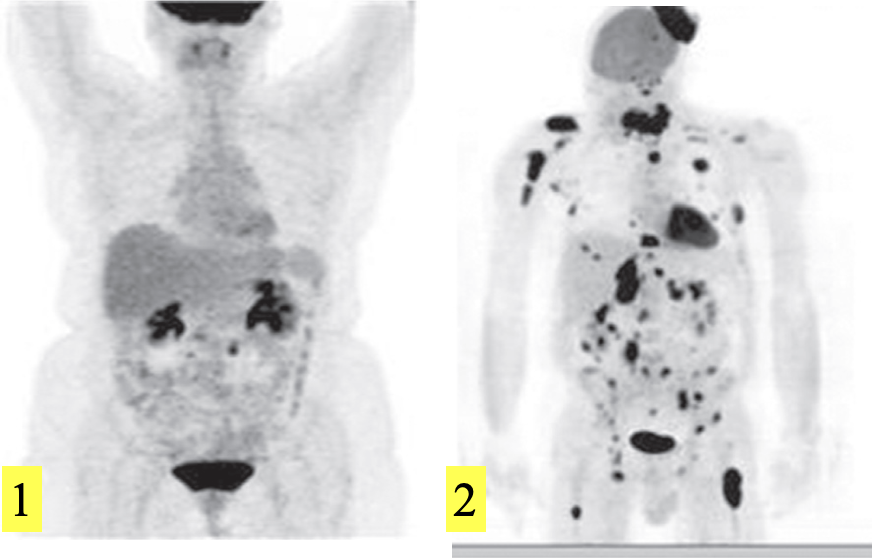

FDG-PET scans, maximum intensity projections.

Normal isotope distribution. There is intense uptake in the brain and the neck uptake is in the tonsils. The FDG is excreted by the kidneys.

Lymphoma, showing multiple visceral, nodal, bone and scalp deposits.